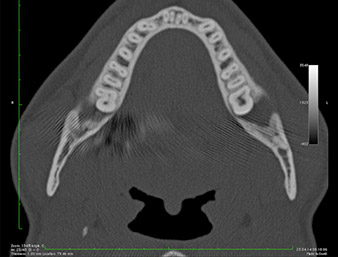

It could be seen in the 3D image (digital volume tomography) that the root remnant was located disto-caudally in the transition from the horizontal to the ascending portion of the mandible (Fig. 2).

Based on his medical history, our patient (non-smoker, 26 years old) had a very good chance of a successful outcome. Due to indication of the root remnant’s close proximity to the inferior alveolar nerve on the OPG, digital volume tomography was used in addition (6).

The very close proximity discovered made it necessary to perform a precise and atraumatic osteotomy. In this case, clinical observations and comparative studies favour piezo surgery which has been available since the end of the 1990s (9-11). Due to the characteristic micro-oscillation of these systems, it is possible to remove bone selectively, thus enabling minimally invasive preparation.